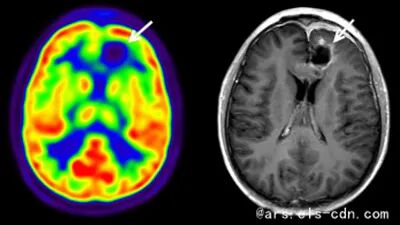

万里云医疗携手医学影像大咖晋晖主任,通过直播与大家一同完成颅内肿瘤的科普分享。颅内肿瘤,可发生于脑组织、脑膜、脑神经、血管等组织,亦可是人体其他部位的恶性肿瘤转移或侵入颅内的肿瘤。根据公开资料描述,此组织肿瘤发病率约是7~10/10万,半数为恶性肿瘤,占人类已知恶性肿瘤的1.5%。因此,前期的影像检查和诊断尤为重要。

♪ 颅内肿瘤分类、临床表现及影像学表现;

♪ 鉴别脑内、外肿瘤的方式和依据;

♪ 在医学影像下,观察胶质瘤 、脑膜瘤、生殖细胞瘤、转移瘤、细胞瘤和脊索瘤等成像表现。